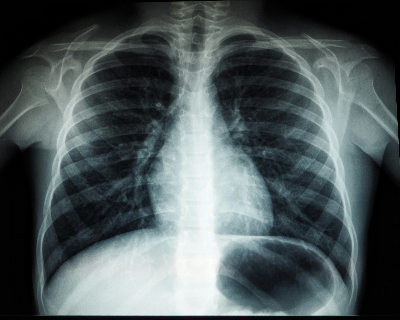

8. 폐암 환자에게 추천되는 이유

폐암 환자들은 항암 치료로 인해 염증 수치가 높고 면역력이 급격히 떨어질 수 있습니다. 커큐민은 이러한 염증을 억제하고, 세포 보호 작용을 통해 회복에 도움을 줄 수 있어 보조요법으로 활용됩니다.